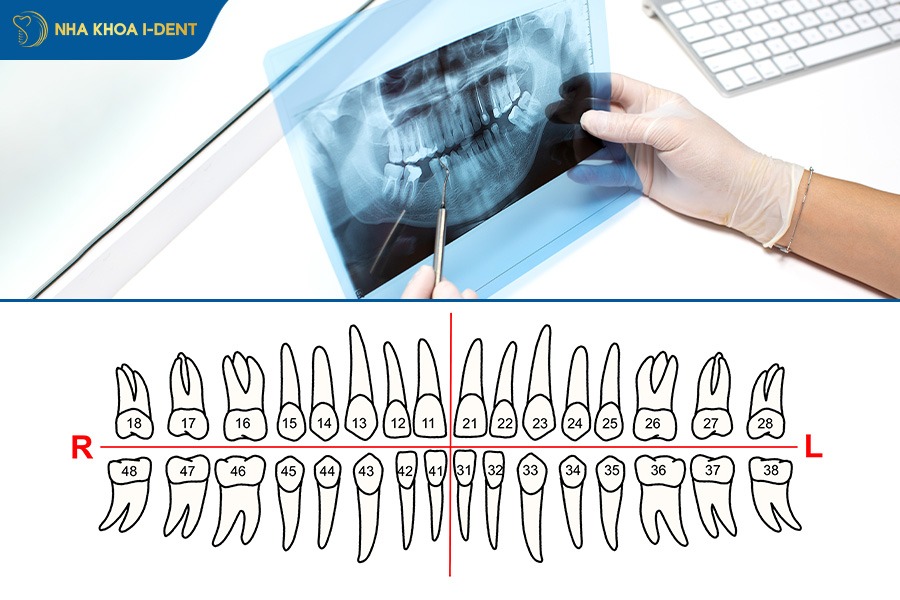

3.2. Thu thập dữ liệu & phân tích hình ảnh số

Để quá trình niềng răng diễn ra thuận lợi, bác sĩ sẽ tiến hành thăm khám tổng quát và chụp phim X-quang để đánh giá tình trạng răng của bệnh nhân như răng bị thưa, hô (vẩu), móm, răng khấp khểnh hay lệch khớp cắn…

Bên cạnh đó, tùy vào mục đích thăm khám mà bác sĩ có thể chỉ định một số kỹ thuật chụp phim khác nhằm giúp việc thu thập dữ liệu tình trạng răng, xương hàm đạt kết quả chuẩn xác, chẳng hạn:

- Chụp phim Ceph/Pan (CT Cone Beam 3D), scan trong miệng 3D bằng máy iTero Lumia.

- Chụp ảnh trong miệng và ngoài mặt.

- Chụp phim Cephalo và Pano xem toàn cảnh các răng, xương hàm.

- Chụp thêm PA nếu có bất đối xứng theo chiều ngang.

- Chụp phim quanh chóp khi cần khảo sát tình trạng răng nhất định, chụp CBCT khảo sát những cấu trúc và răng mọc bất thường như răng dư và răng mọc ngầm.

- Lấy dấu nghiên cứu khi cần.

Toàn bộ dữ liệu trên (bao gồm cả ảnh trong miệng và ngoài mặt) là nền tảng số hóa giúp mô phỏng chính xác tình trạng răng và xương hàm.